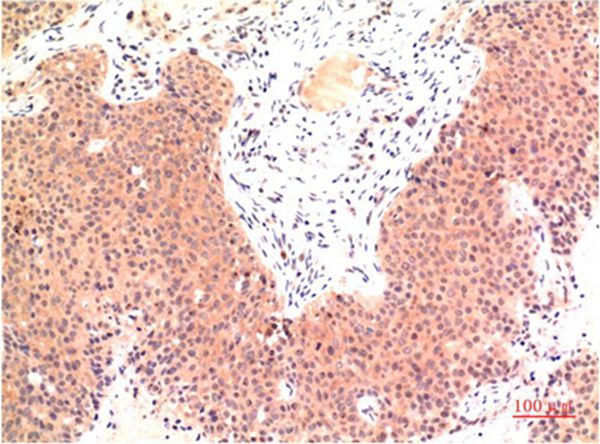

分类: 科研抗体货号: P43528别名: Speckle-type POZ protein (HIB homolog 1) (Roadkill homolog 1)应用: WB,IHC反应种属: Human,Mouse,Rat